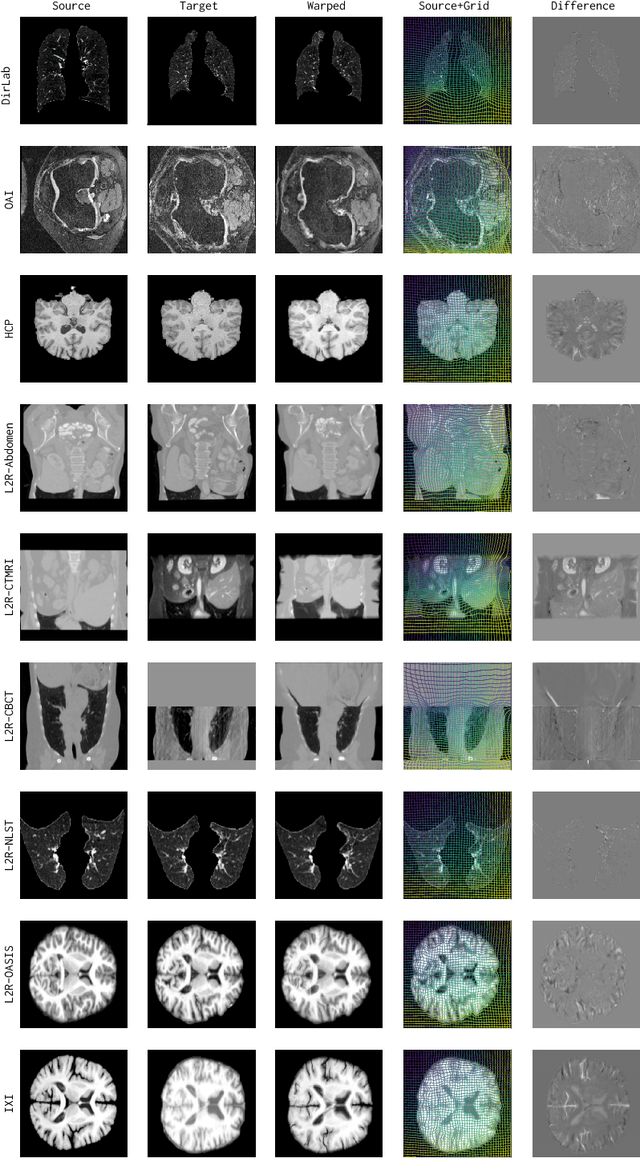

Abstract:Conventional medical image registration approaches directly optimize over the parameters of a transformation model. These approaches have been highly successful and are used generically for registrations of different anatomical regions. Recent deep registration networks are incredibly fast and accurate but are only trained for specific tasks. Hence, they are no longer generic registration approaches. We therefore propose uniGradICON, a first step toward a foundation model for registration providing 1) great performance \emph{across} multiple datasets which is not feasible for current learning-based registration methods, 2) zero-shot capabilities for new registration tasks suitable for different acquisitions, anatomical regions, and modalities compared to the training dataset, and 3) a strong initialization for finetuning on out-of-distribution registration tasks. UniGradICON unifies the speed and accuracy benefits of learning-based registration algorithms with the generic applicability of conventional non-deep-learning approaches. We extensively trained and evaluated uniGradICON on twelve different public datasets. Our code and the uniGradICON model are available at https://github.com/uncbiag/uniGradICON.